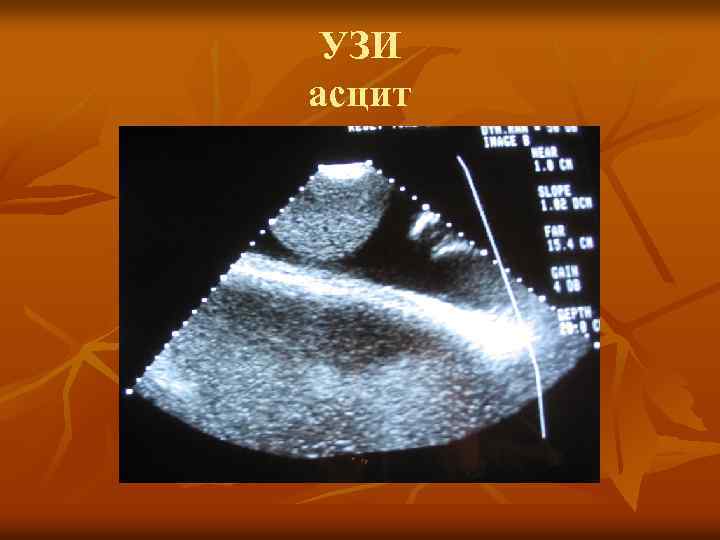

УЗИ асцит УЗИ асцит

асцит асцит